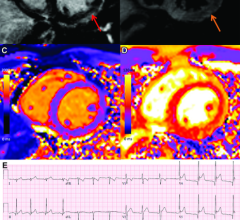

News | Cardiac Imaging

June 24, 2022 — The Radiological Society of North America (RSNA) reports that Coronary Artery Calcium (CAC) scoring…